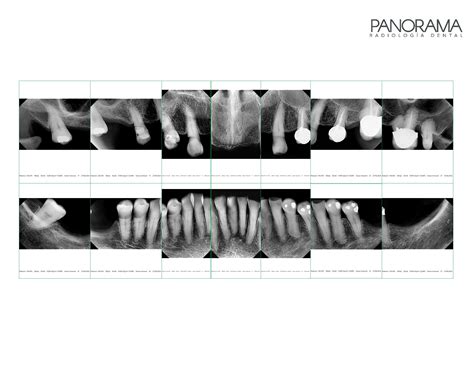

Es bueno saber si al realizarse una radiografía dental en el embarazo, existe algún riesgo. Por lo general, estas radiografías permiten diagnosticar lesiones y enfermedades en las encías o en las raíces así como planificar el tratamiento correspondiente.

Entonces, estas radiografías panorámicas no resultan perjudiciales para el feto porque no se expone directamente a la radiación. Los rayos x que podrían perjudicar el feto serían las radiografías abdominales, en estas el bebé se expone de forma directa.

Y si la dosis de radiación fue mínima, es poco probable que el feto manifieste alguna complicación. En caso de que no sea nada urgente, el odontólogo puede esperar a que termine el embarazo para hacer el diagnóstico con la panorámica. Es posible que una embarazada se haya realizado unos rayos x panorámicos sin saber qué estaba en estado gestacional.

También se considera seguro realizar radiografías dentales durante el embarazo si estuviesen indicadas, ya que la dosis de radiación es mínima y puntual, además de utilizar la protección radiológica adecuada (delantal plomado).